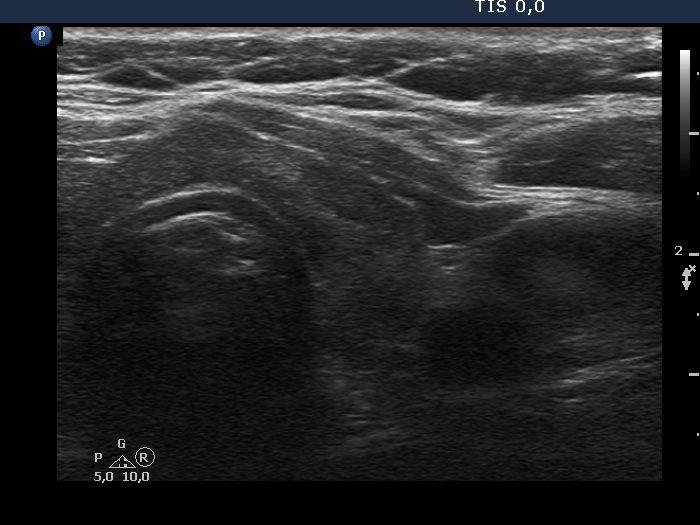

Examination in 2013 (first row of images):

Clinical data. A 50-year-old woman was referred for evaluation of a nodular goiter. The patient has been treated for hypothyroidism for 16 years.

Palpation: Both lobes were a bit firm, no nodule was palpable.

Laboratory test: TSH 4.01 mIU/L on daily 100 microgram levothyroxine.

Ultrasonography. The thyroid was minimally/moderately hypoechoic and had several discrete minimally/moderately hypoechoic lesions.

Cytology was performed from the lesion in the central part of the right lobe and resulted in Hashimoto's thyroiditis.